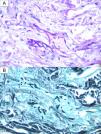

Un adolescente hospitalizado de 16 años diagnosticado de anemia falciforme, presentaba 4nódulos purpúricos de 5mm de diámetro, localizados en el cuello, el miembro superior derecho y el abdomen (fig. 1), de un día de evolución. El paciente había sido sometido a 2alotrasplantes sucesivos de progenitores hematopoyéticos, el último 9 días antes, y tenía un recuento de 0 neutrófilos por microlitro, por lo que estaba recibiendo un tratamiento profiláctico con anfotericina B liposomal a 3mg/kg/día. Estaba afebril. Había presentado una neumonía consolidativa días antes con una PCR de un lavado broncoalveolar negativa para hongos, aunque el marcador fúngico galactomanano había aumentado de 0,17 a 5,71. Ante la sospecha de infección fúngica invasiva, se realizaron biopsias para tinción con calcoflúor, además de para examen histológico y cultivo fúngico. También se tomaron hemocultivos. En la tinción de calcoflúor se observaron estructuras fúngicas, por lo que se aumentó la dosis de anfotericina B a 5mg/kg/día y se añadió isavuconazol. En la tinción con hematoxilina-eosina se apreció, en la dermis media, un grupo de hifas hialinas y septadas de localización intravascular y en la dermis inmediatamente adyacente al vaso (figs. 2 y 3). En el cultivo fúngico creció Fusarium verticillioides sensible a anfotericina B, posaconazol y voriconazol. Los hemocultivos fueron negativos. Se cambió isavuconazol por voriconazol y se aportó filgrastim con lo que se obtuvo una recuperación parcial de la neutropenia, una respuesta clínica excelente, la resolución del cuadro y una reducción de los niveles de galactomanano a 0,18.

Una vez sospechada la infección, se debe poner en marcha inmediatamente el proceso diagnóstico, que incluye la biopsia con una tinción fúngica inmediata (como calcoflúor o KOH), el examen histológico y el cultivo, la toma de hemocultivos y pruebas radiológicas para valorar la afectación pulmonar y de los senos1. Los hemocultivos solo son positivos en un 40% de los pacientes con una fusariosis diseminada6, quizá debido al empleo de antifúngicos profilácticos o a las condiciones de recogida de la muestra. El diagnóstico definitivo requiere una histología que demuestre la presencia de estructuras fúngicas en el interior de los vasos, lo que explica la necesidad del examen microscópico urgente, ya sea con tinciones rápidas o con cortes histológicos congelados. Aun así, el cultivo es clave para filiar el tipo de hongo (Aspergillus y Fusarium son idénticos al microscopio) y para conocer su sensibilidad.